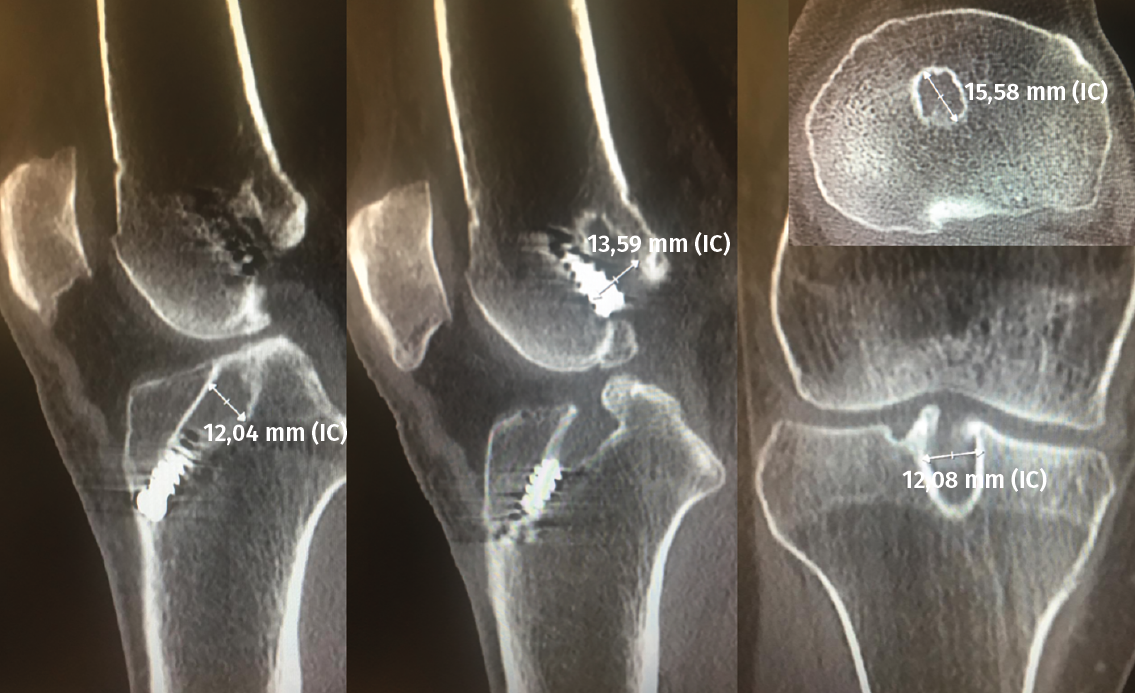

El estudio mediante TC, tanto en 2D como en las reconstrucciones actuales en 3D, va a ser de gran utilidad para poder identificar la posición de los túneles óseos tibial y femoral, la dirección de ambos y, finalmente, el grado de dilatación y la morfología de los mismos. Estos aspectos van a ser claves para poder planificar la cirugía de revisión en uno o dos tiempos (Figuras 3 y 4).

Figura 3. La tomografía computarizada en 2D mediante cortes axiales, coronales y sagitales permite conocer tanto la dirección como la morfología de los túneles previos, así como medir el grado de dilatación de los mismos para planificar la cirugía de revisión.

En cuanto al grado de dilatación de los túneles óseos, la mayoría de los autores consideran que una dilatación de los mismos superior a 12-14 mm hace recomendable realizar la cirugía en dos tiempos(29,30,31). No obstante, algunos trabajos más recientes no observaron diferencias significativas comparando los resultados funcionales en recambios en un solo tiempo con presencia de túneles óseos superiores e inferiores a 12 mm y con un seguimiento de 5 a 15 años(32).